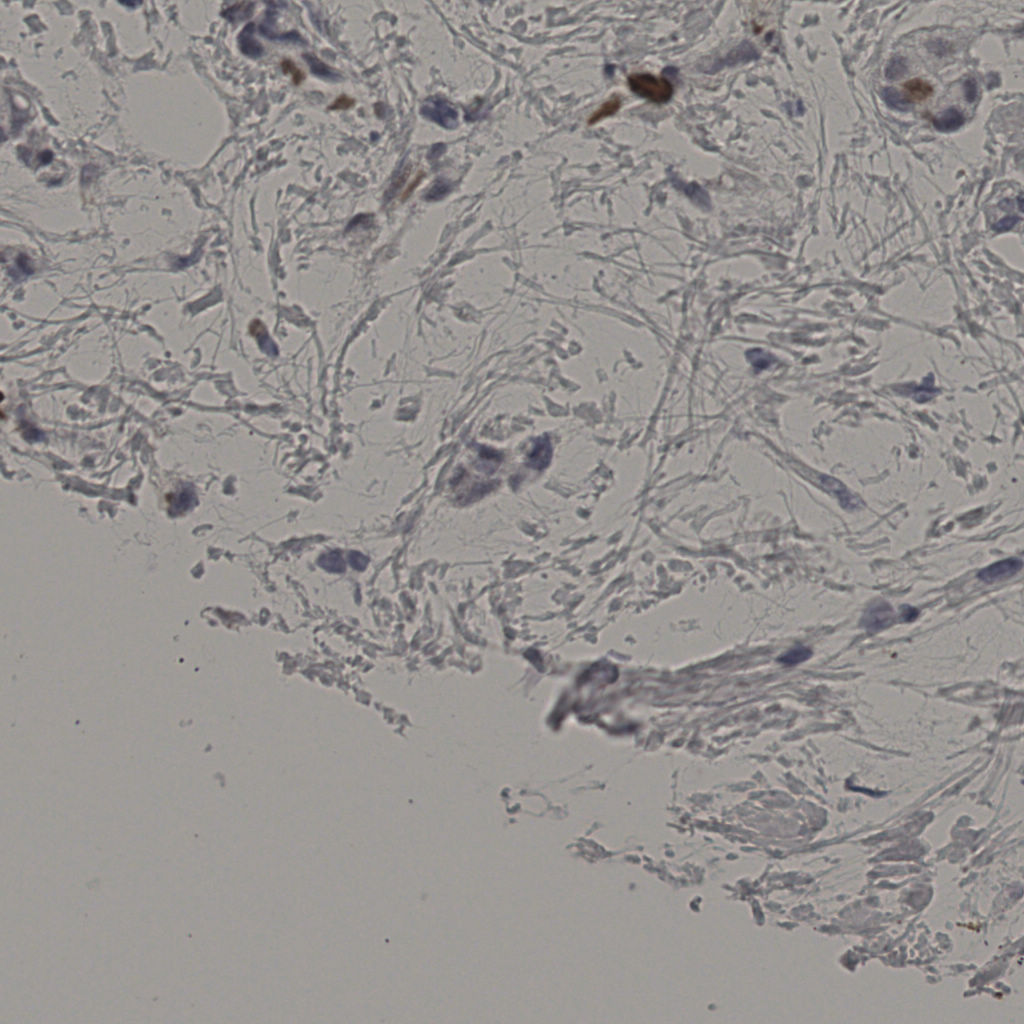

5.31%

Ki67 指数

阴 19502 阳 1093